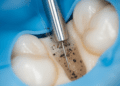

Terapia periodontal

Se a recessão estiver associada à doença periodontal, a primeira etapa é o controle da infecção, com limpeza profunda para remoção da placa bacteriana e do cálculo dental, chamada de raspagem e alisamento radicular.